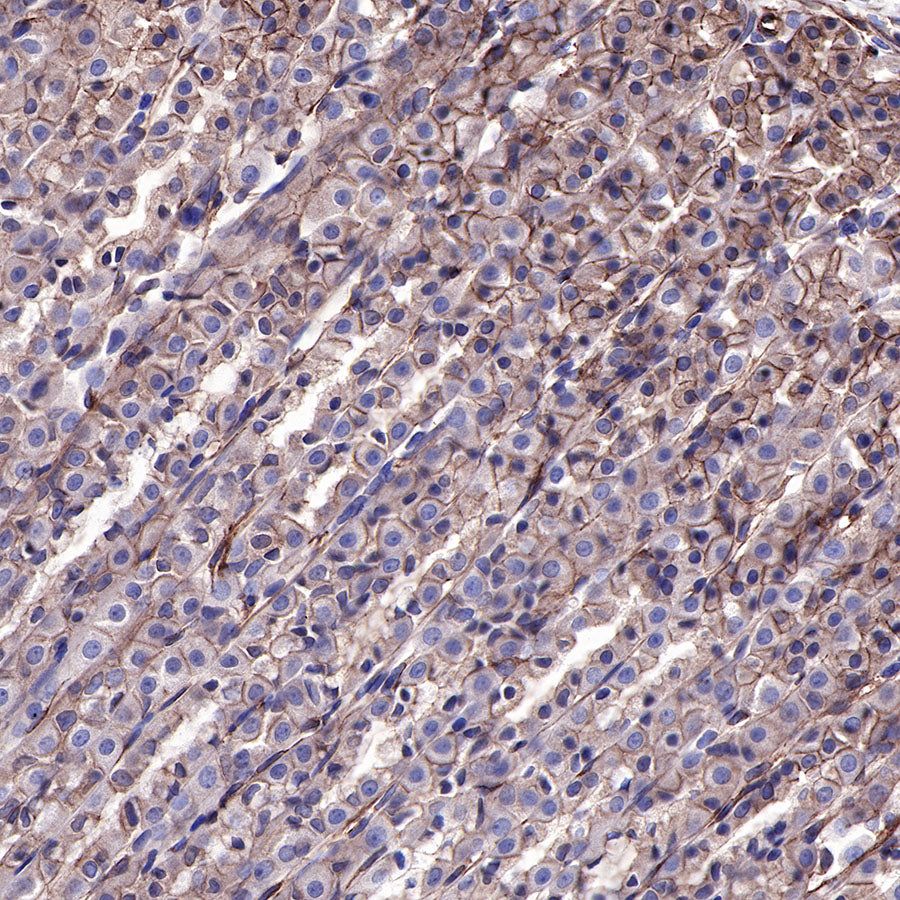

Immunocytochemistry

ICC shows positive staining in A431 cells. Anti-EGFR antibody was used at 1/500 dilution (Green) and incubated overnight at 4°C. Goat polyclonal Antibody to Rabbit IgG - H&L (Alexa Fluor® 488) was used as secondary antibody at 1/1000 dilution. The cells were fixed with 4% PFA and permeabilized with 0.1% PBS-Triton X-100. Nuclei were counterstained with DAPI (Blue).